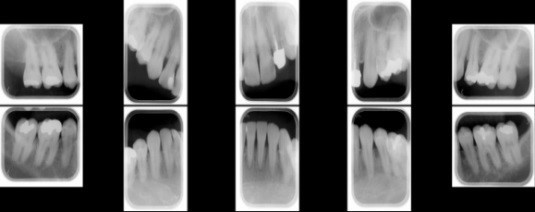

デジタルレントゲンでは、口腔内全体を細かく撮影します。(残存歯数により撮影枚数に変化があります。)肉眼では見えない歯肉に覆われた歯石や、歯の根の形状、むし歯や歯周病の有無や進行度合いを鮮明な二次元の平面画像で確認します。

歯周病治療3週間集中プログラムの症例一覧